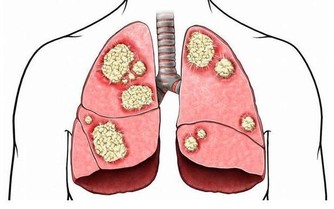

柑橘類水果是維生素C的重要來源,而維生素C是一種強有力的抗氧化劑,

有助於保護細胞免受自由基的侵害,這甚至可以幫助我們預防心血管疾病和癌症。